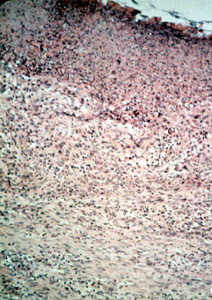

| Este

microfotografía se observa el área ulcerada en la base de la

invaginación y muestra exudado inflamatorio, tejido fibroso reactivo y tejido de granulación.

| Periférico a

la ulceración el tejido del tipo predominante que comprende la mayoría

de la lesión, es el tejido conjuntivo fibroso bastante denso con un número

moderado de los vasos sanguíneos. Note la inflamación crónica

perivascular tan común en

las lesiones reactivas. Los fibroblastos son uniformes a lo largo hay

considerable colágeno denso. Con esta microfotografía usted

puede determinar que la única forma de eliminar la lesión es con la

biopsia por escisión. |